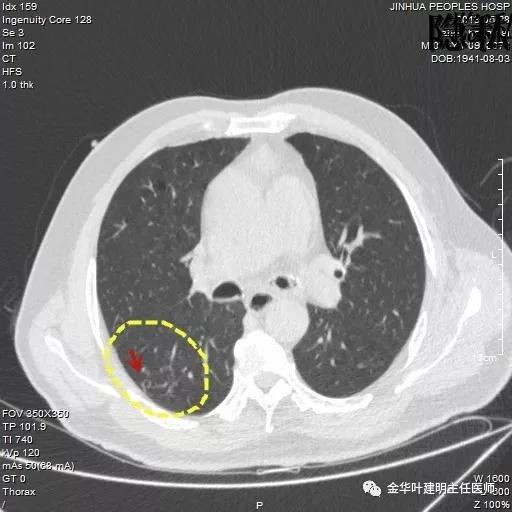

考虑恶性,那么就得考虑住院并行手术治疗,入院后再进一步查靶扫描,结果如下:

是不是囊腔型腺癌?周围病灶,有空腔,有磨玻璃成份,当然要考虑,但我觉得因为似乎是以往是空腔性病变,今年其内部分填充了实性成分,要考虑粘液腺癌可能为大。当然反正都得手术切除治疗。